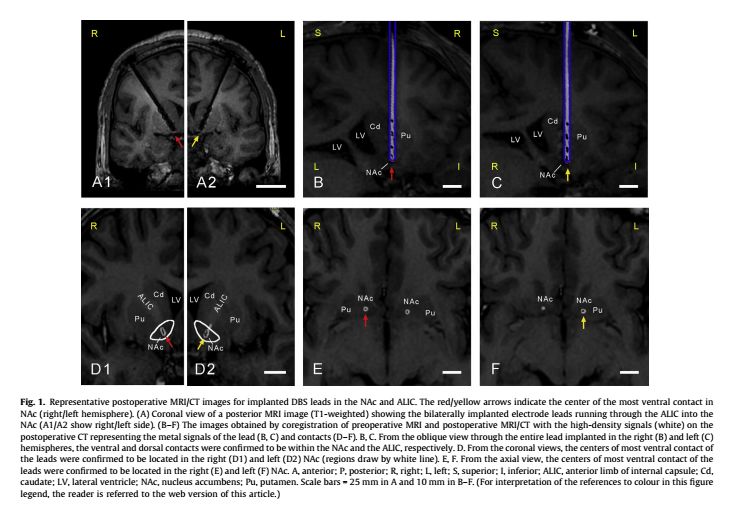

研究纳入了7例接受深部脑刺激(DBS)治疗的海洛因成瘾患者,通过DBS电极记录NAc和ALIC的局部场电位(LFPs),对其进行功率谱分析,并分析了不同频段功率谱能量积分值与患者神经心理量表分值间的相关关系。研究中采用的脑深部刺激电极是苏州景昱医疗器械有限公司提供的专用于阿片类药物成瘾患者防复吸治疗的植入式神经刺激系统,包括:植入式神经刺激器(型号:1181)、神经刺激系统电极导线套件(型号:1242)等。设备的主要作用机理是:一根电极可以承担一侧的伏隔核和内囊前肢的两个功能区的不同参数的输出。植入式神经刺激器通过与电极的配合使用,可以同时对两个功能区域输出完全不同的刺激参数(频率、幅值、脉宽)。神经刺激器的“双通道双频神经调控芯片”能够在一根电极上对两个功能区输出完全不同频率的电刺激脉冲。

参与研究的7例患者均根据第五版精神疾病诊断手册中物质依赖的诊断标准(DSM-V)明确诊断。植入刺激器前经过临床脱毒治疗,通过尿检吗啡、纳洛酮的阴性结果证实。植入的电极通过ALIC并达到手术靶点NAc。所有患者均接受相关的神经心理量表测评:其中视觉模拟评分(VAS)用来评估患者的渴求海洛因的程度。该临床研究前期已在ClinicalTrials.gov(NCT01274988)登记,目前已完成11例(包括本文报道的7例患者),查新显示为世界上相关研究的最大病例组,单个患者的操守时间已超过3年,整体操守率超过60%,防复吸效果令人满意。